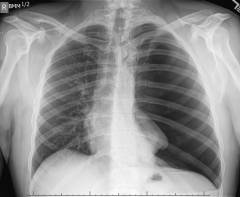

- Внешний осмотр. Оценивают цвет кожи (при нарушении дыхания она приобретает сероватый оттенок), ощупывают грудную клетку и расположенные под кожей лимфатические узлы.

- Выслушивание грудной клетки при помощи фонендоскопа (аускультация). Врач оценивает дыхание, выявляет имеющиеся нарушения.